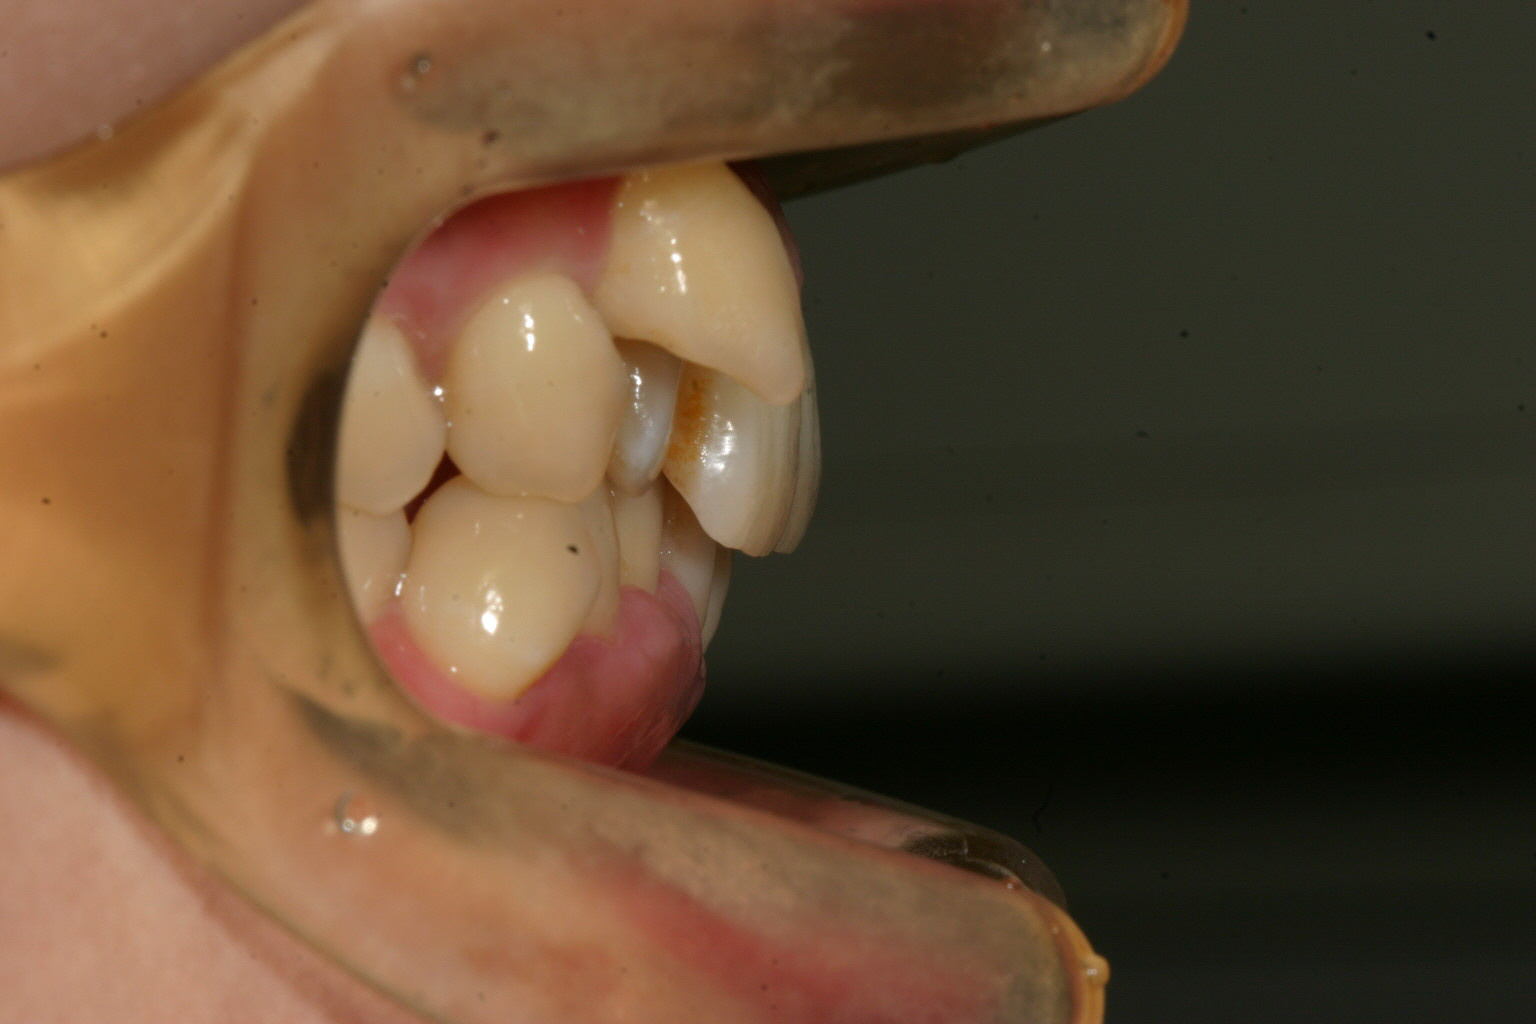

八重歯が完全に歯列からはみ出してますね~ この様な場合冬になって唇乾くと八重歯に唇が引っかかって下がって来ないなんて経験有りませんか? そこで八重歯の後ろ隣の小臼歯を抜歯して出来た隙間に 犬歯を移動する事にしました。

これだけ突出してたら冬場唇が乾燥すると唇が引っかかって下がって来ません。同じような症例の患者様なら経験有ると思います。

この様に犬歯が上に有る場合インビザライン単独ではなかなか引っ張り出す事は苦手なんです。

こういった場合には上下の歯の表面にボタンを貼り付けてインビザラインを付けたままゴムをかけて頂くと簡単に犬歯の挺出を行う事が出来ます。